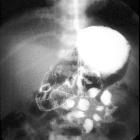

Infant with

bilious vomiting. AP image from an upper GI exam shows a dilated air and contrast filled stomach and duodenum. The duodenal-jejunal junction is normally positioned at the level of the duodenal bulb and to the left of the spine at L1.The diagnosis was normal bowel rotation.